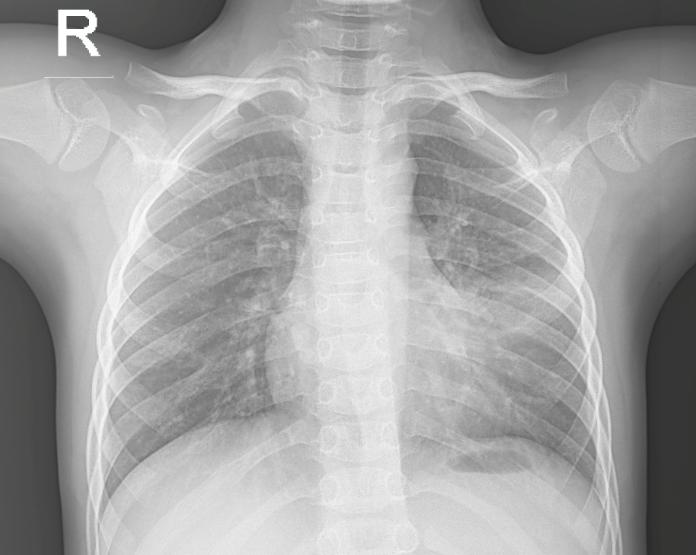

Hình ảnh Xquang BN viêm phổi thùy

Phim X quang, cũng tương tự như phim chụp hình, được đặt phía sau bộ phận cơ thể cần chụp. Máy X quang sẽ chiếu tia X qua bộ phận cơ thể này. Các tia X nào gặp phim sẽ tạo hình. Càng nhiều tia X đến phim thì hình ghi được càng đen hơn. Vì vậy, các bộ phận đặc của cơ thể cản rất nhiều tia X sẽ cho hình trắng (ví dụ như xương) trong khi những bộ phận cơ thể rỗng hoặc đầy khí sẽ cho hình đen (ví dụ như phổi). Các mô mềm (ví dụ như cơ hoặc các tạng đặc trong cơ thể) sẽ cho hình ảnh có mức độ xám khác nhau tuỳ theo đậm độ của chúng.

Ví dụ, một khối u phổi đặc hơn nhu mô phổi, sẽ cho thấy hình ảnh bóng mờ trên X quang. Một khối u vú đặc hơn mô vú bình thường sẽ cho thấy hình ảnh bóng mờ trên X quang vú (nhũ ảnh)

Tụ dịch, trong phổi hoặc ruột chẳng hạn, có thể sẽ cho hình ảnh bóng mờ với độ xám khác với màu đen chứa đầy khí của nhu mô phổi bình thường hoặc ruột trống.